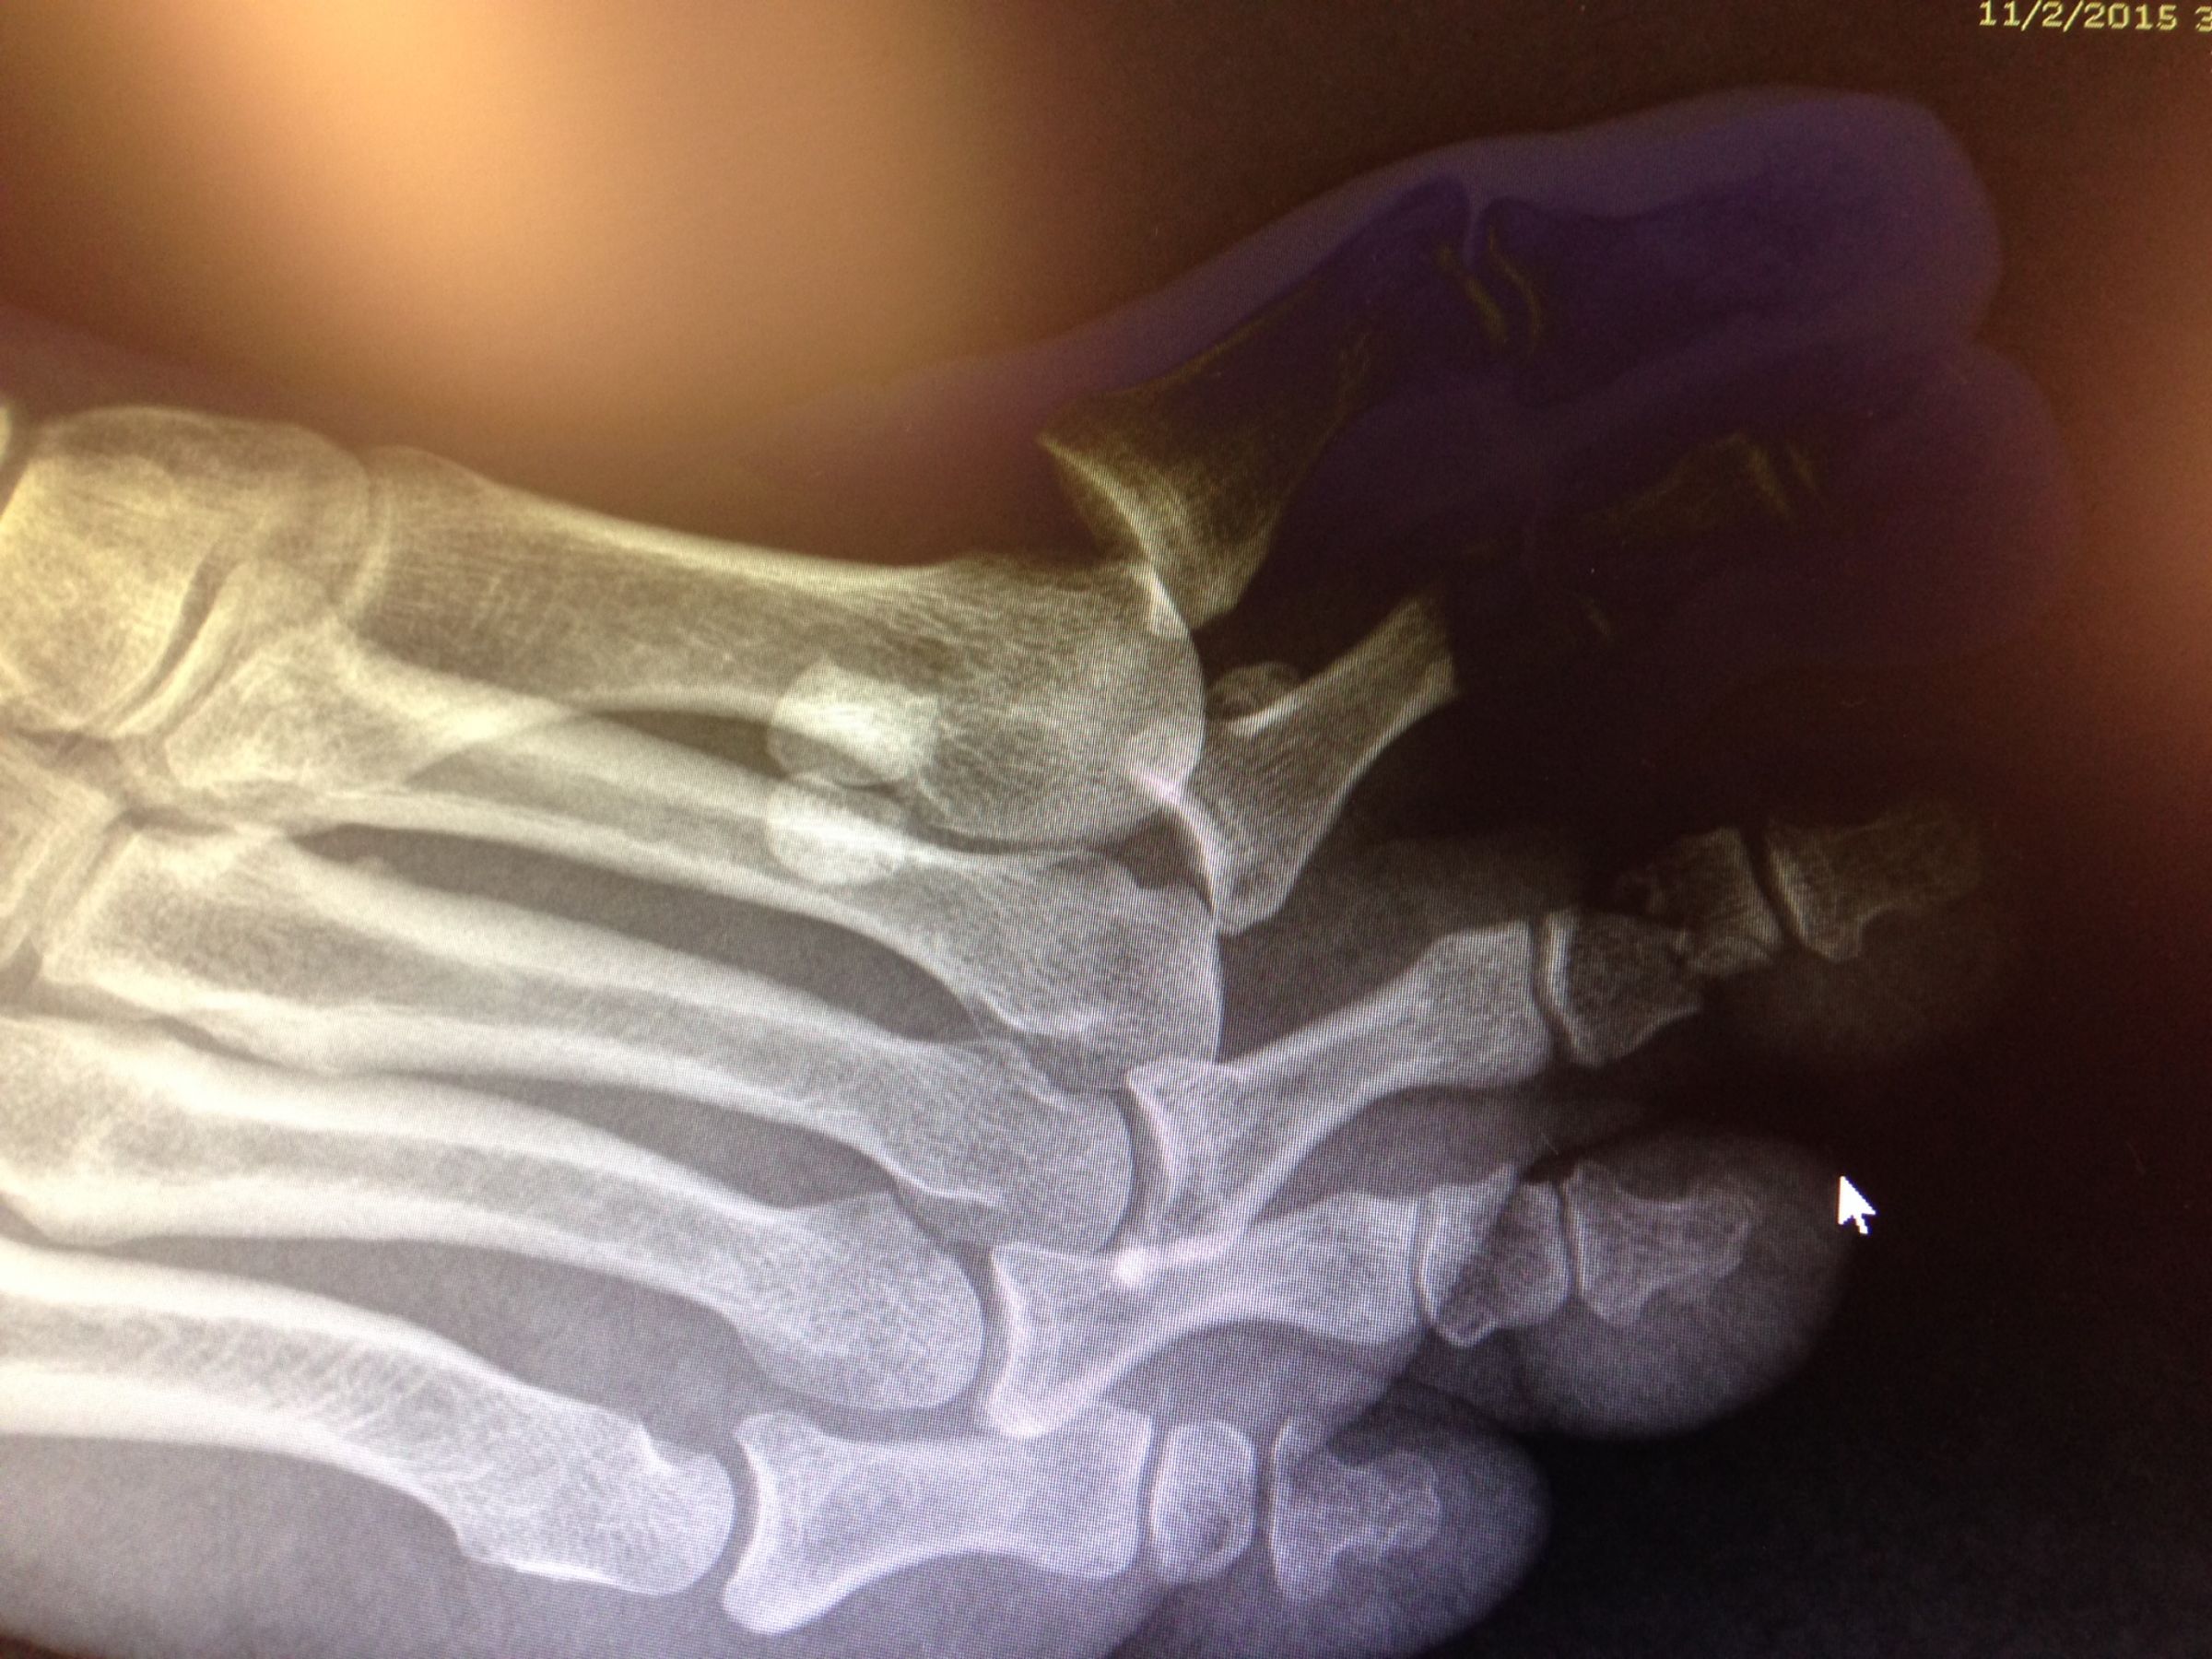

Broken wrist